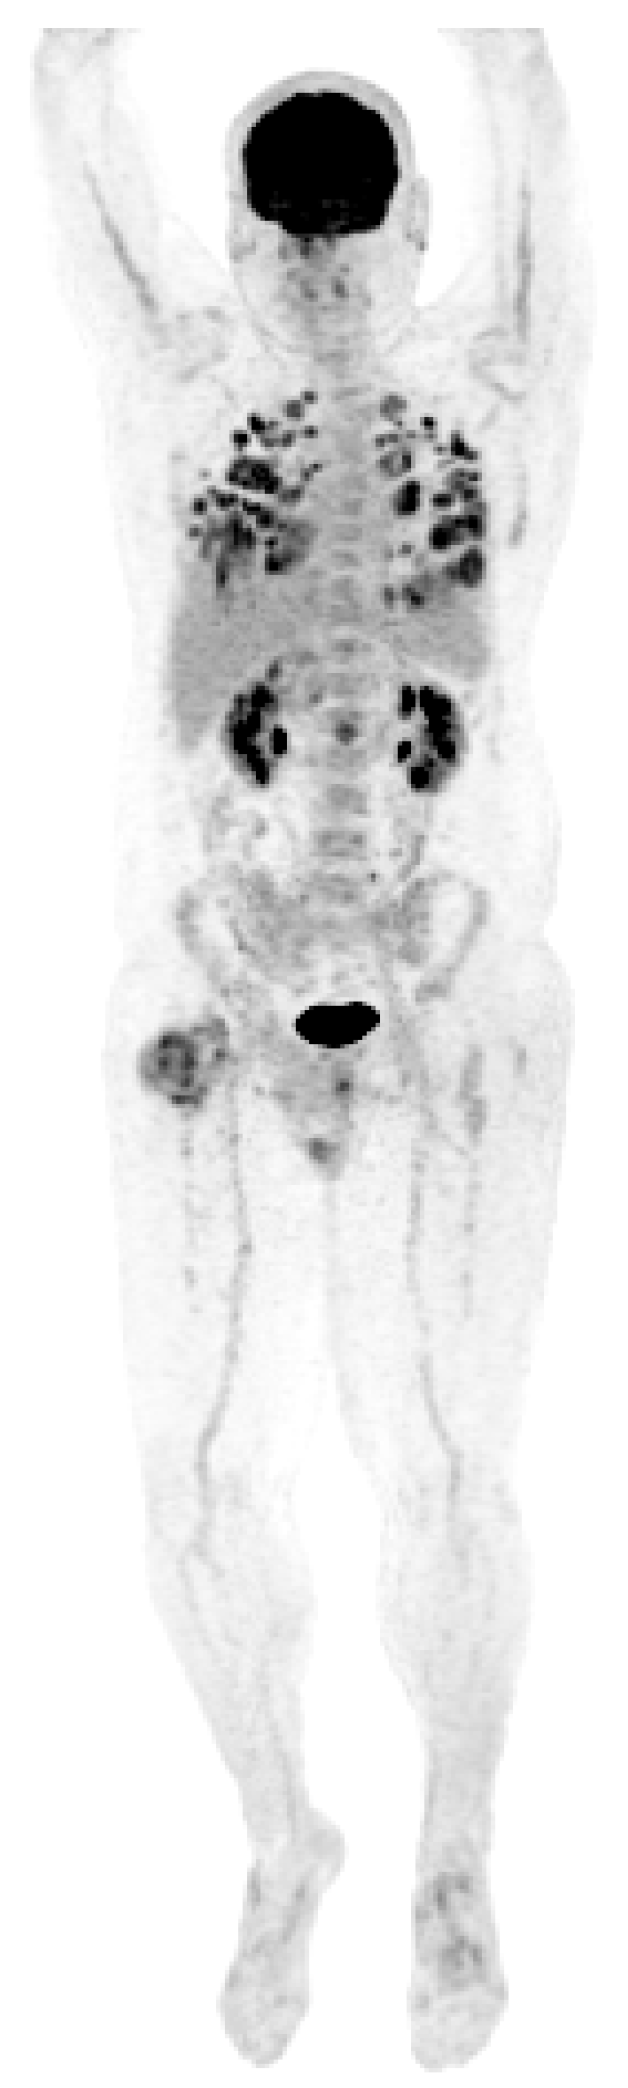

| Patient NSGCT Type | Status | Pathology of Primary | Stage at Time of Diagnosis | S-YSTemic Chemo | Date: Pathology after Chemo |

|---|---|---|---|---|---|

| 1 ETT | Cured | 100% S (elevated AFP) | IIX | BEP x1, VIP x3, paclitaxel (docetaxel), doxorubicin, gemcitabine, | 6/2012: 90% T, 10% ETT + adenocarcinoma |

| 2 S-YST | Cured | 5% E, 90% S, 5% Y | IIIC | BEP x4 | 5/2018, 4/2019, 4/2020: 99% S-YST + 1% T |

| 3 ETT | Cured | 80% ETT, 20% T | IIC | BEP x3 | 1/2018: T w/minute ETT |

| 4 S-YST | Died | NA Y in met | IIIC | BEP x4 | 9/2016: T 1/2021: S-YST |

| 5 ETT | Died | 100% E | IIIA | BEP x1, EP x3, TIP x4, POMB x2, ATP x4, TIP x1/HDC + SCT | 7/2019: Embryonal 11/2019: ETT 1/2020: Choriocarcinoma |

| 6. ETT | Died | 99% E, 1% T | IIIA | BEP x3, TIP x3, ATP | 9/2018: E, C 7/2019, 8/2019: 60% ETT + squamous cell carcinoma |

| 7 S-YST | Died | NA i(12p)+ in met | IIC | BEP x2, XELOX, ATP x2 | 8/2019: S-YST (Unresectable) |